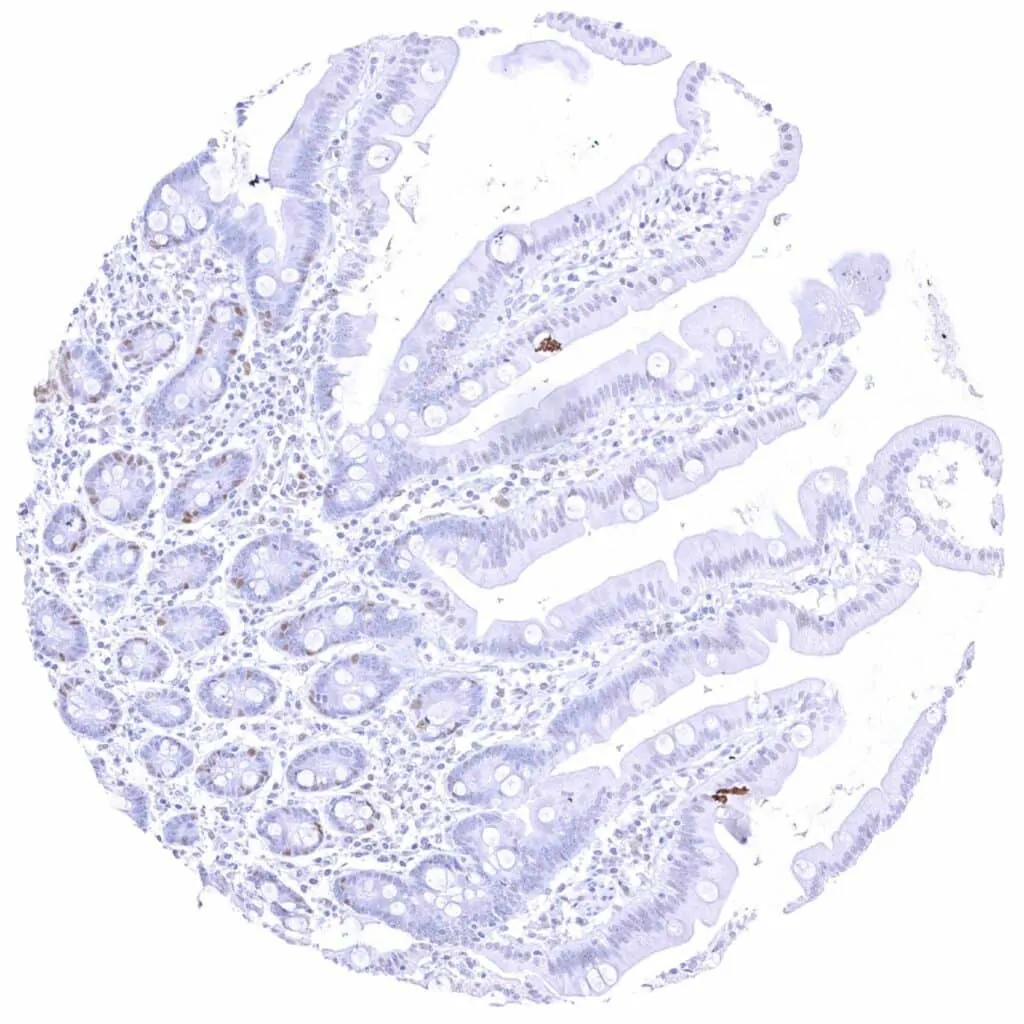

Colon descendens, mucosa – Weak to moderate Cyclin E1 staining of a large subset of crypt cells